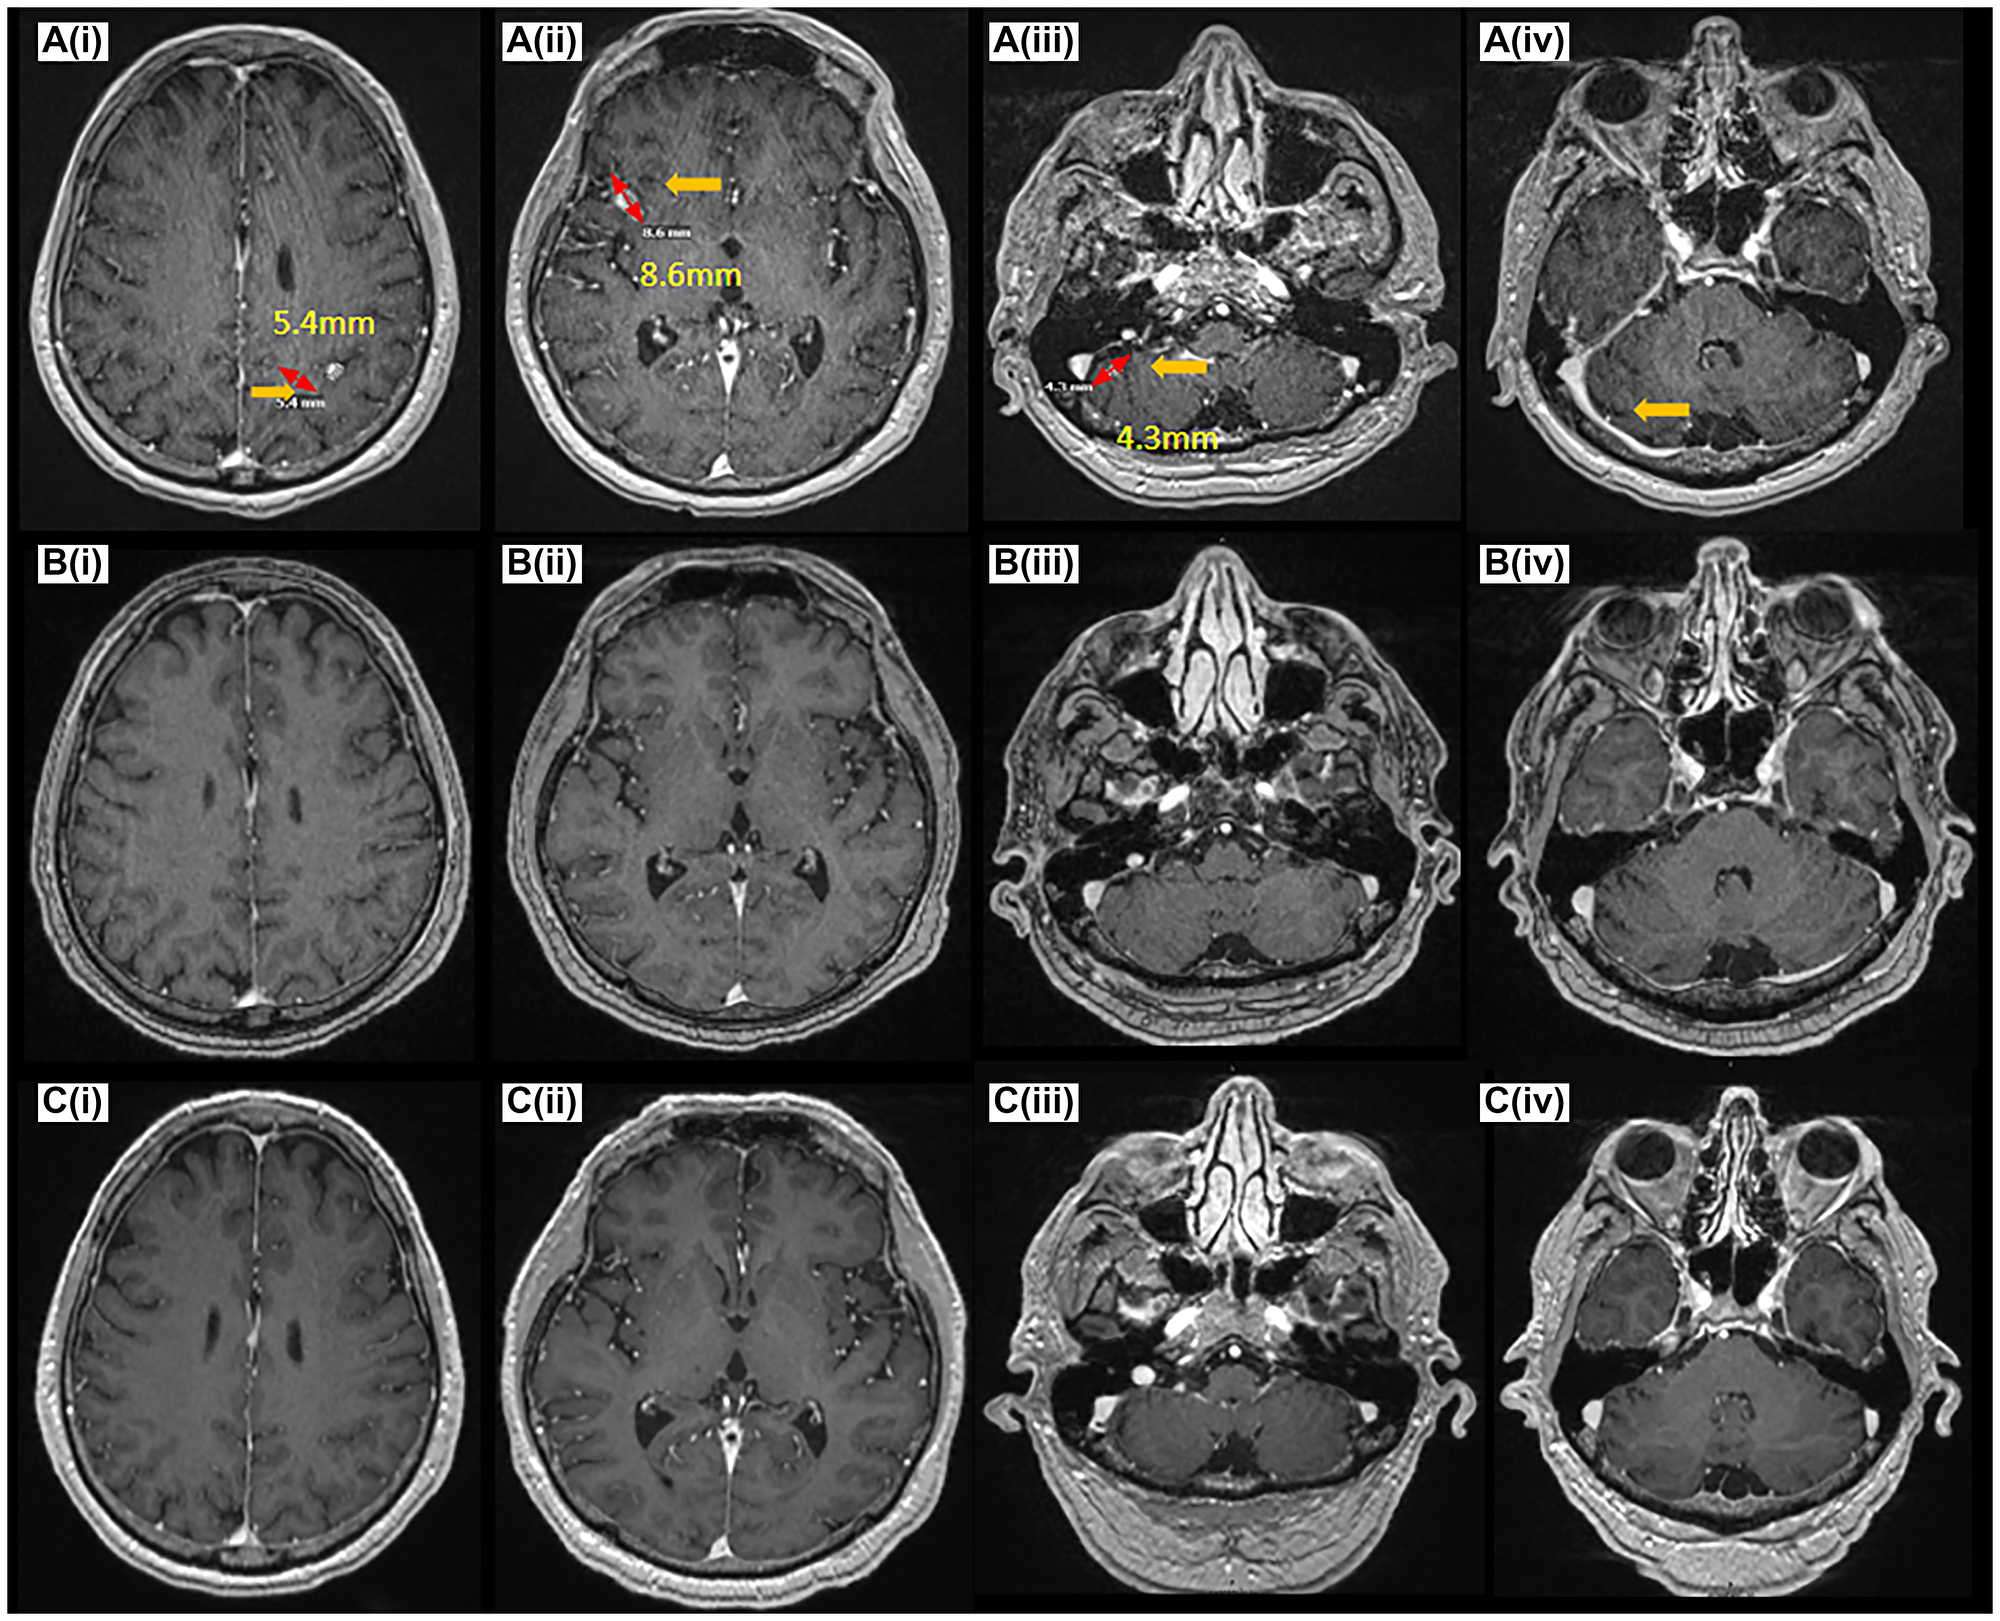

CNS disease response on amivantamab

Figure 3: CNS disease response on amivantamab.

MRI Brain at the time of pre-treatment (A(iiv)), 6 months (B(iiv)), 19 months (C(iiv)) post-treatment demonstrating complete resolution of CNS disease at 6 months (B(i–iv)), and 19 months (C(i–iv)).